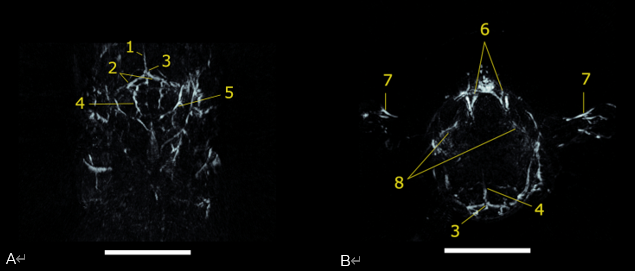

神經(jīng)成像

10 毫米厚的 (A) 冠狀和 (B) 橫向最大強(qiáng)度投影板,從 750 nm 掃描重建 PAI 體積。1) 上矢狀竇,2) 橫竇,3) 竇匯合處,4) 腦動脈,5) 耳動脈,6) 頸靜脈,7) 肱動脈,8) 眼動脈。比例尺為 5 毫米。